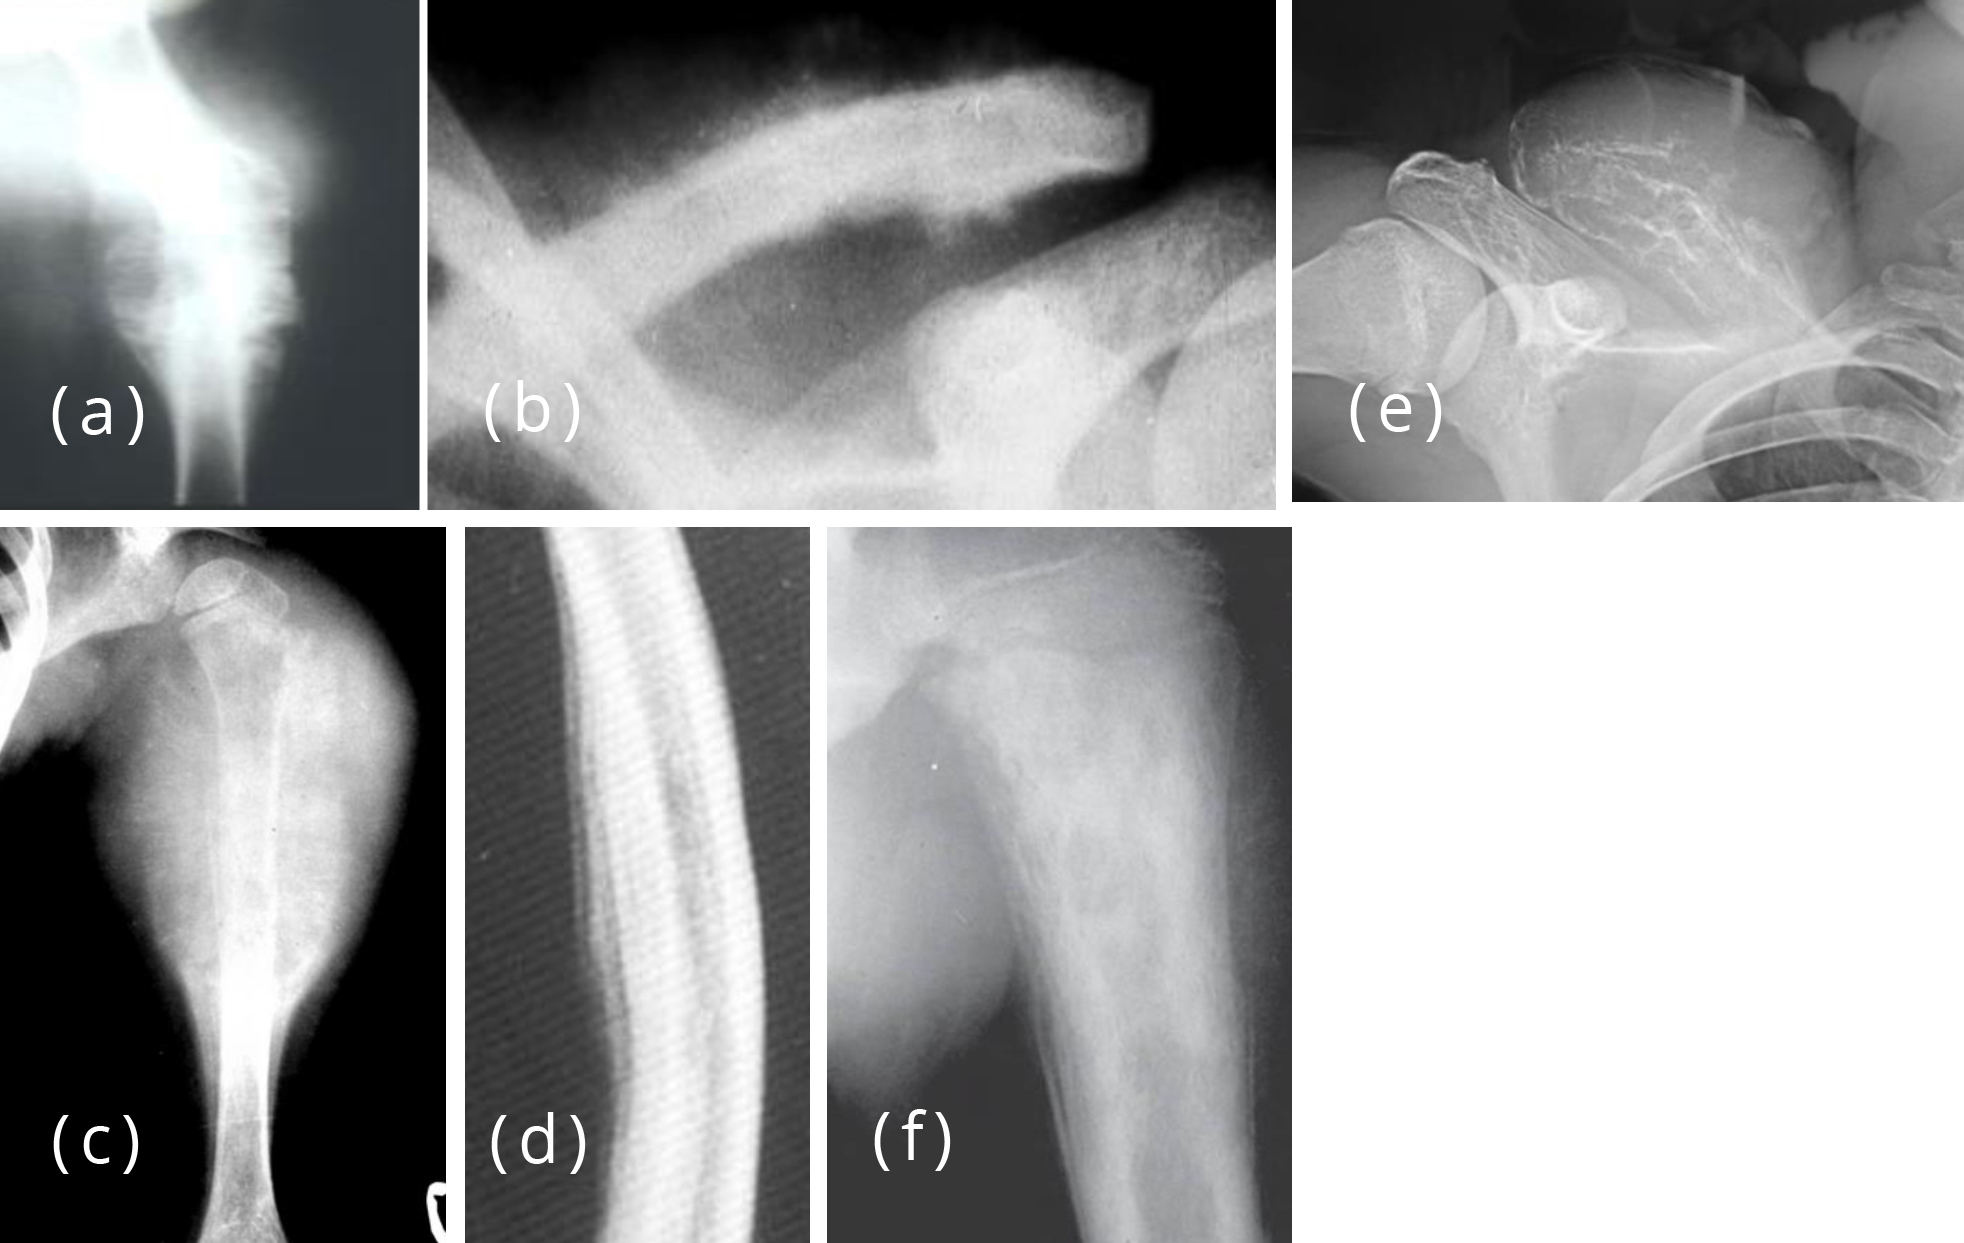

periosteal reactions solid, lamellated, sunburts, codman's Radiology Periosteal Reaction Dental Tumor, infection, trauma, certain drugs, and some arthritic conditions can elevate the periosteum from. This poster will review the gross and cellular anatomy of the periosteal membrane and a range of periosteal responses. Patterns of periosteal reaction, both in morphology and distribution, are key to distinguishing benign or physiologic periosteal reaction from types of periosteal. Periosteal reaction results when cortical. Periosteal Reaction Dental.

From www.pinterest.co.uk

Periosteal reaction Periosteal Reaction Dental Patterns of periosteal reaction, both in morphology and distribution, are key to distinguishing benign or physiologic periosteal reaction from types of periosteal. The ultimate goal of any dental treatment is the regeneration of lost tissues. Proliferative periostitis is a rare disease, and represents new bone formation. Periosteal reaction results when cortical bone reacts to one of many possible insults. The. Periosteal Reaction Dental.

From www.semanticscholar.org